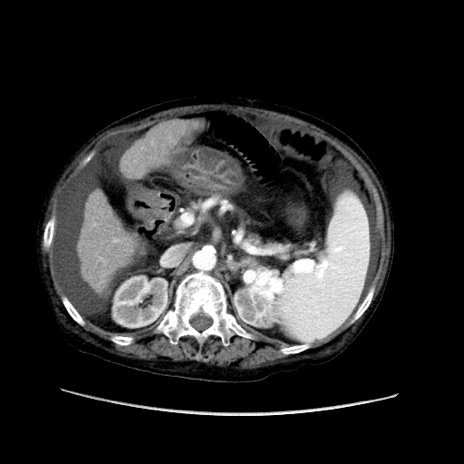

症例31(横断像)

【症例】80歳代 女性

【主訴】腹部膨満感

【現病歴】他院にて肝硬変にてフォロー中。1週間前から便秘、腹部膨満感、臍部腫瘤あり受診となる。

【既往歴】肝硬変

【身体所見】腹部膨隆あり、皮膚変化なし、疼痛なし。

【データ】WBC 4600、CRP 0.25